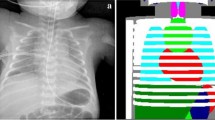

The dose area product (DAP), measured in Gy/cm2, for every radiograph was extracted from the hospital Computerised Radiology Information System (CRIS). The Effective Dose (ED), measured in millisieverts (mSv), is the unit by which radiation risk is quantified [21]. The ED for every radiograph was individually calculated from the DAP using specific conversion coefficients for the area of the body irradiated [18]. The specific cumulative ED for each child was compiled. This process is outlined in Fig. 1.